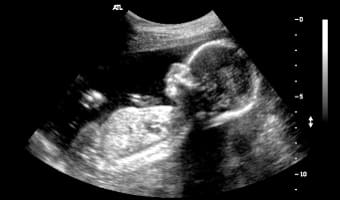

Как выглядит киста яичника на УЗИ

В гинекологии киста представляет собой полую опухоль, чаще всего доброкачественного характера, заполненную жидкостью.

Главным признаком кисты яичника при ультразвуковом исследовании является образование полого отростка на его поверхности. В отличие от нормального фолликула, который изменяется в течение менструального цикла, киста остается неизменной. Кроме того, такое образование обычно имеет больший размер.

На ультразвуковом снимке киста яичника отображается в виде черного пятна, размеры которого варьируются от 3 до 20 см.